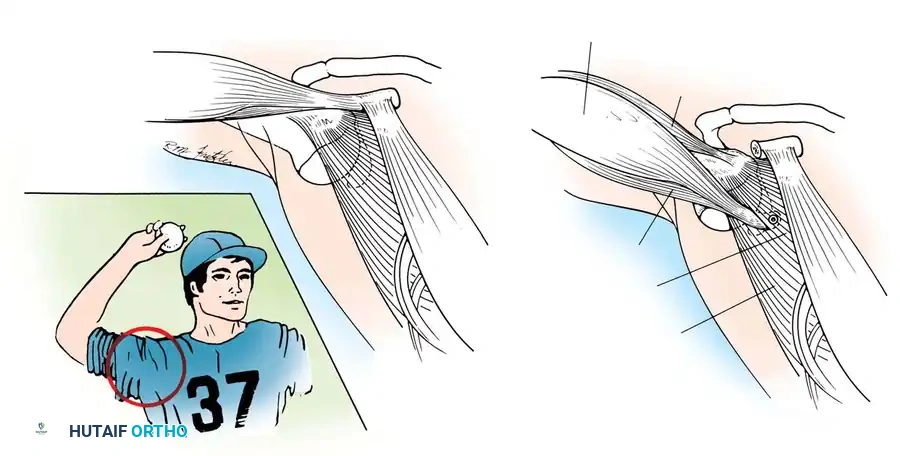

Dynamic Stabilizers and Concavity Compression

The musculature surrounding the shoulder provides essential dynamic stability. The deltoid produces primarily vertical shear forces, tending to displace the humeral head superiorly. To counteract this, the intrinsic muscles of the rotator cuff provide compressive forces. Lippitt and Matsen described "concavity compression," wherein the dynamic contraction of the rotator cuff compresses the humeral head into the concave glenoid socket. Loss of the labrum reduces this stabilizing effect by up to 20%.

Glousman et al. highlighted that synchronous eccentric deceleration and concentric contraction of the rotator cuff and biceps are vital for stability during mid-ranges of motion. Asynchronous fatigue from overuse or incompetent ligaments leads to microtrauma. MRI studies frequently reveal fatty infiltration and thinning of the subscapularis tendon in chronic recurrent anterior instability.

Furthermore, scapulothoracic kinematics play a massive role. Rowe, Kummel, and later Lippitt and Matsen emphasized that synchronous mobility of the scapula ensures the glenoid is optimally positioned beneath the humeral head, converting potential shear forces into compressive forces. Jobe and Glousman advocated for rigorous strengthening of scapular stabilizers (serratus anterior, trapezius, rhomboids) in overhead athletes. Proprioceptive feedback, mediated by Ruffini end organs and Pacinian corpuscles within the capsule (as demonstrated by Vangsness et al.), is also critical for dynamic neuromuscular control.